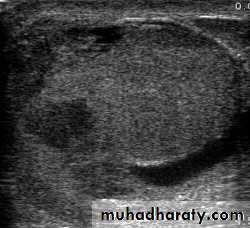

U/S is the investigation of choice

Doppler ultrasound scan will confirm the absence of the blood supply to the affected testis

Investigations: Scrotal Doppler U/S

Scrotal U/S

U/S scanning of the testis

Urinary tract ultrasound scan to diagnose reflux